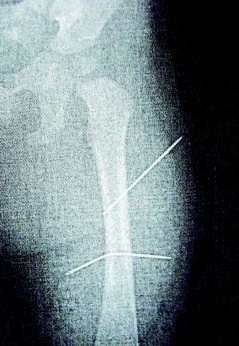

X光片中清楚可見兩根長針深深刺入女娃左大腿內側。圖片來源:臺灣《聯合報》

中新網3月20日電 據臺灣《聯合報》報道,桃園縣一女子因受不了9個月大外甥女頻頻哭鬧,將兩根長達5厘米縫衣針刺進女娃左大腿,還拿蒼蠅拍猛打她背部造成瘀青,昨天被桃園法院判處8個月徒刑,緩刑3年,需到指定公益團體或小區提供60小時義務勞務。

判決書指出,該女子去年照顧年僅9個月大外甥女,因外甥女哭鬧不停,情緒失控下拿家中縫衣針兩根,連刺入女娃左大腿內側,完全沒入皮下組織。

隔月27日,該女子又見外甥女哭鬧不停,拿蒼蠅拍朝著外甥女背部連打數十下,造成女娃背部瘀傷。經女娃母親發現后送醫救護,院方為女童進行X光片照射后,才發現女娃左大腿里竟有兩根縫衣針。